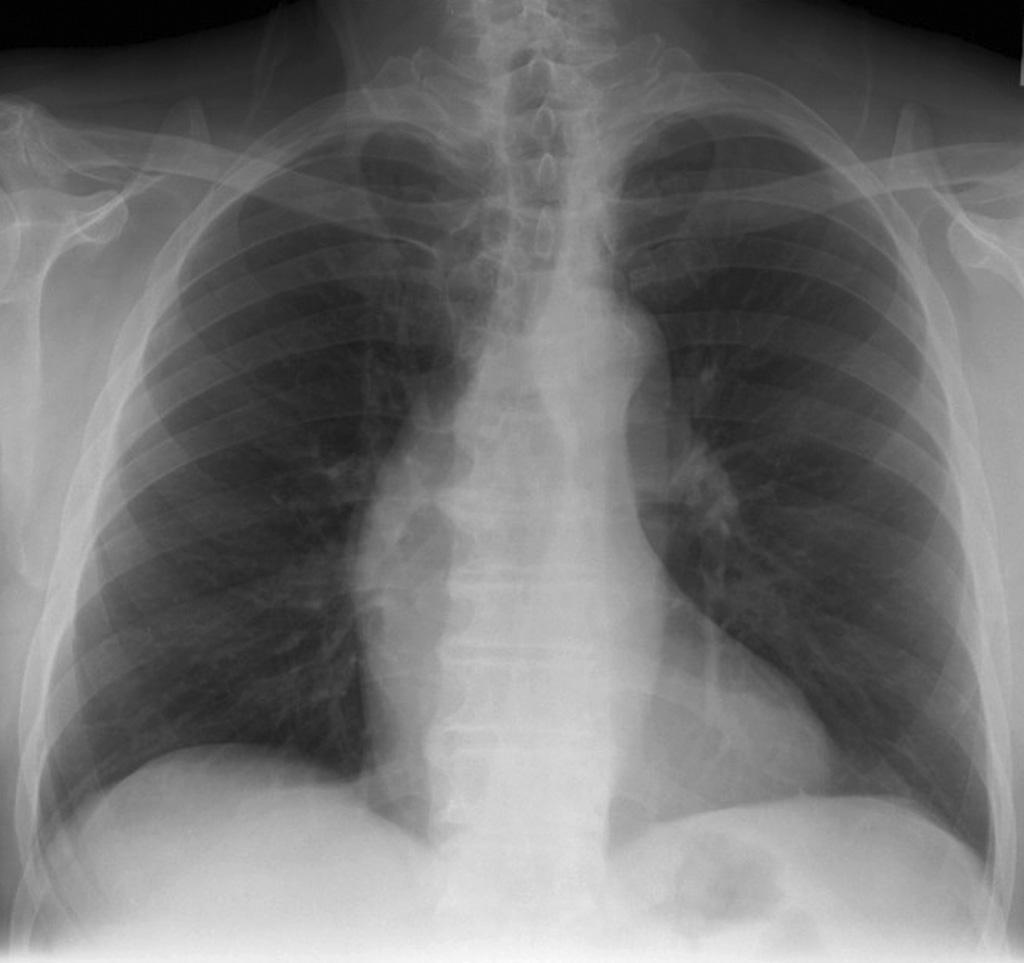

What is going on in this CXR?

These radiographs show atelectasis of the right middle lobe

You can tell that this is atelectasis rather than a consolidation by the downward displacement of the minor fissure

Fissures move towards a collapsed lobe, as do the trachea and heart, and the ipsilateral diaphragm.